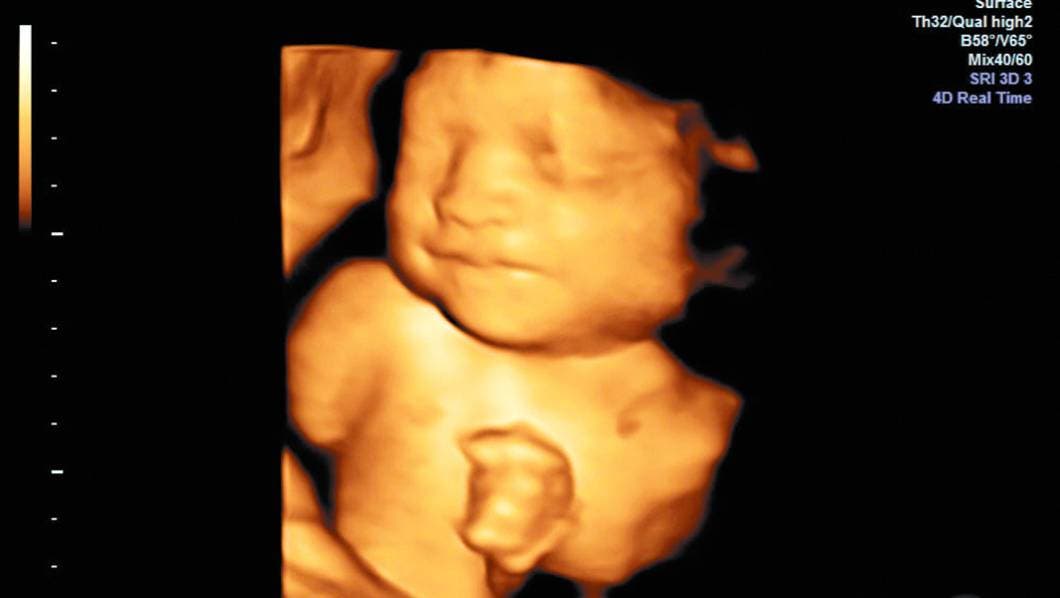

A detalle. El investigador busca que mediante software el ultrasonido detecte posibles riesgos de parto prematuro.

CUERNAVACA, MORELOS.- En el recién creado Laboratorio de Ultrasonido Médico del Instituto de Física de la UNAM, Iván Rosado desarrolla técnicas de ultrasonido para detectar condiciones que generan partos prematuros espontáneos.

"Para que un ultrasonido convencional tenga ese uso se debe entender cómo interacciona el equipo médico con el tejido para obtener una respuesta", explicó.

"El equipo produce una onda de ultrasonido, la cual interacciona con alguna propiedad física del tejido; esa interacción es diferente en tejido sano o enfermo", dijo el científico.